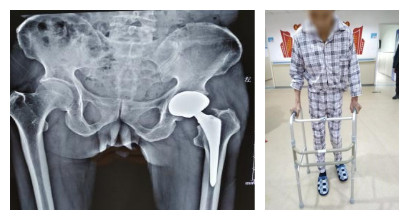

术后换药切口: 术后第3天复查骨盆X线:

术后2周骨盆X线: 术后2周患者下地行走:

全髋置换术是骨科大手术之一,风险较大,技术要求高。 该病例创伤严重,从手术到出院,从卧床到行走,仅历时不到2周,且术后功能恢复良好,病人及家属极度满意。此次手术的实施成功,又一次再现骨科专业医疗综合实力。